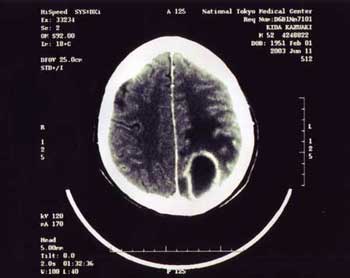

平成15年6月13日、脳に菌が入り炎症が生じて膿が溜まる「脳膿瘍(のうのうよう)」(=写真下)で、死亡率4〜5割と宣告され、緊急開頭手術を受ける。手術が成功しても、術後、脳の菌に抗生剤が効かない可能性もあり、大量の抗生剤の副作用によって肝臓、腎臓障害で死亡する可能性もあると宣告される。

写真 脳膿瘍(のうのうよう)。細菌感染で左脳に非常に大きな膿瘍ができている。これにより、両目とも右半分が見えない、計算ができない、漢字が書けない、右手足の麻痺などの脳障害が生じていた。主治医からは、手術後もこれらの脳障害は残る可能性があると宣告された(平成15年6月11日)